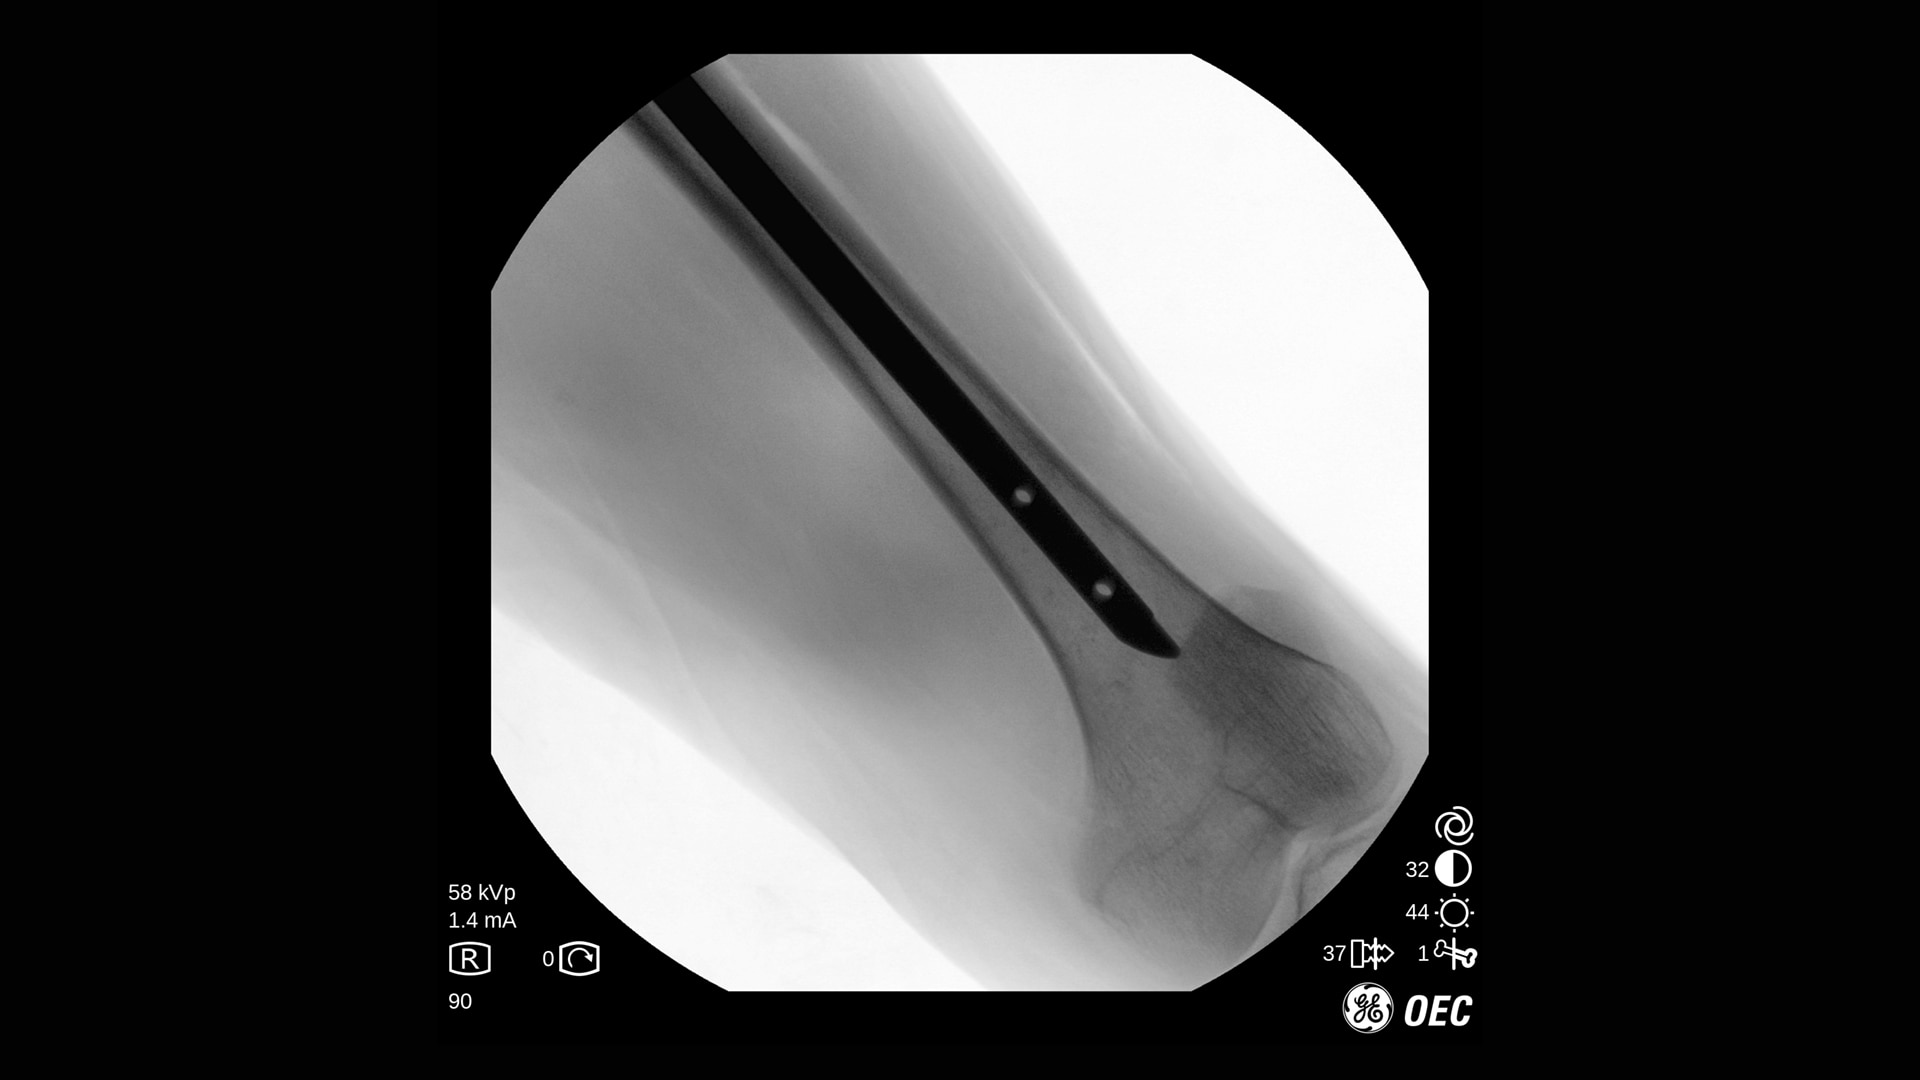

OEC One CFD – Präzision und Übersicht in kompaktem Design

Erleben Sie klare Bilddetails mit Flachfelddetektor, OEC-Bildverarbeitung und 4K-Display.

Die Bildqualität ist bei verschiedenen Verfahren und Verfahrenseinstellungen essenziell, besonders auf engem Raum. Mit OEC One CFD erleben Sie die Bildqualität, die sie von den OEC mobilen C-Bögen erwarten, sowie die klinische Vielseitigkeit, die bei einem mobilen All-in-One-C-Bogen mit zwei Detektorgrößen benötigt wird.

Der OEC One CFD liefert gestochen scharfe Bilddetails – erfasst mit einem Flat-Panel-Detektor und dargestellt auf einem 27" 4K-UHD-Monitor direkt am OP-Feld.

Optimieren Sie Bildqualität und Dosis mit Live-Zoom, Adaptive Dynamic Range Optimization (ADRO), Bewegungsartefakt-Unterdrückung und weiteren intelligenten Bildverarbeitungsfunktionen.